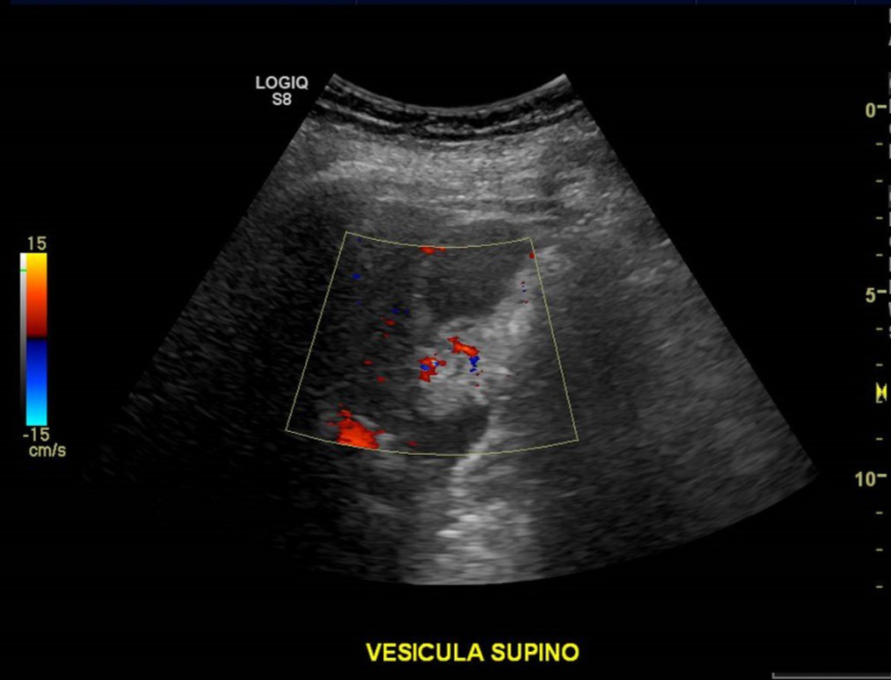

• Pólipo vesicular de grandes dimensiones, con señal Doppler, adherido a pared, no móvil. De mayores dimensiones que en examen anterior.

Vesícula biliar de paredes finas, con bilis ecogénica y cálculos en su lumen, el de mayor tamaño, mide 18 mm.  No hay Murphy ecográfico. En relación a su pared, se observa una lesión ecogénica, pseudonodular, de bordes irregulares, mide 26 x 25 mm, vascularizada.

Masa polipoidea vesicular, de probable etiología primaria.